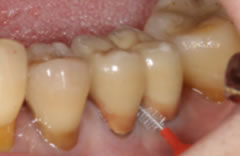

歯周病が進むと、歯肉が退縮して歯が長くなったように見えてしまいます。

この状態を改善できる治療法が「歯肉移植術」です。上あごからご自身の歯肉を切り取り、患部に移植することで、退縮した歯肉を回復させることができます。